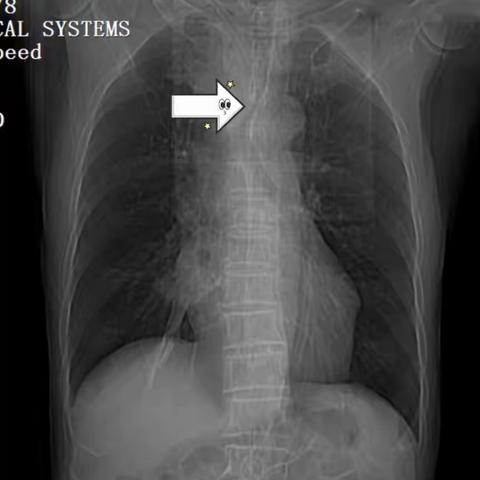

主动脉弓旁小细胞肺癌粒子植入术后纵隔血肿